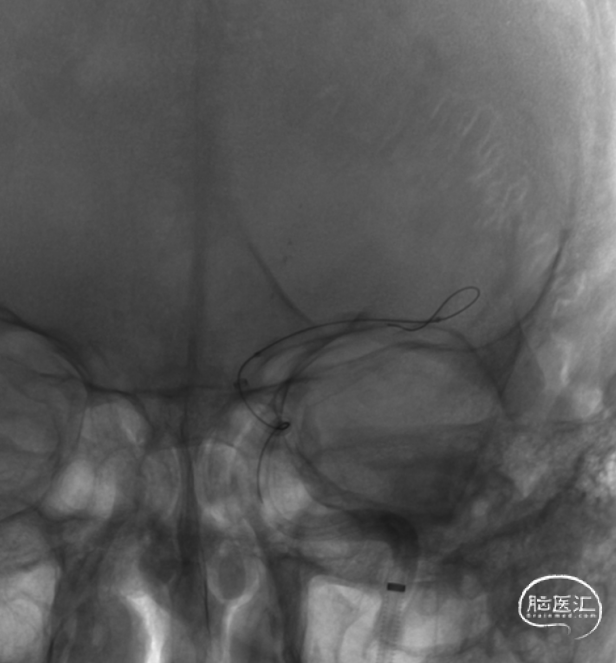

通过微导丝带入微导管,微导丝成袢通过血栓段,然后将微导管往远端输送,跨过血栓段,回撤微导管。

造影确认,闭塞段血流恢复,提示微导管首过效应阳性,残留颈内动脉交通段重度狭窄,串珠样改变,考虑原位狭窄,予替罗非班针微泵维持。

球扩前造影。

白驹®颅内球囊导管 2.0*15mm到位,造影确认。